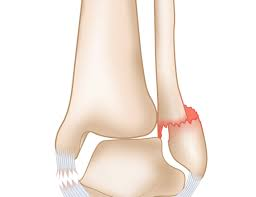

part that is broken

Medial malleolus

Broken bit

Lateral malleolus